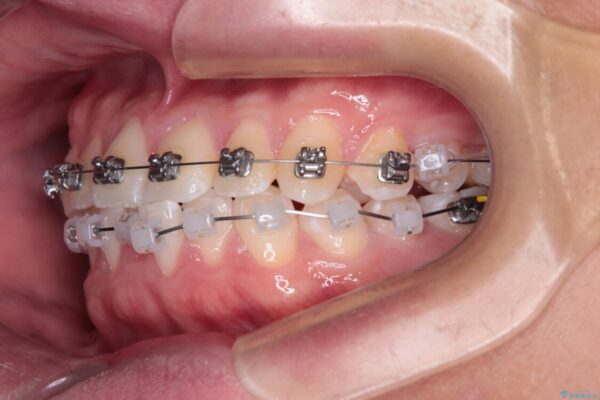

治療途中

• 前歯のガタガタ・奥歯のかみ合わせ(シザーズバイト)を改善|1年半で完了したメタルブラケット矯正 治療途中画像

・上顎左右の第二大臼歯が頬側へ転移し、シザーズバイト(scissors bite)の状態

・上顎左側第二小臼歯が90度捻転しており、噛み合わせに影響

・奥歯のシザーズバイト改善には、口蓋側にアンカースクリュー(TAD)を設置し、矯正用ゴムで内側に牽引

・捻転した第二小臼歯は、ワイヤーと矯正用ゴムの力を用いて正しい位置へ回転移動